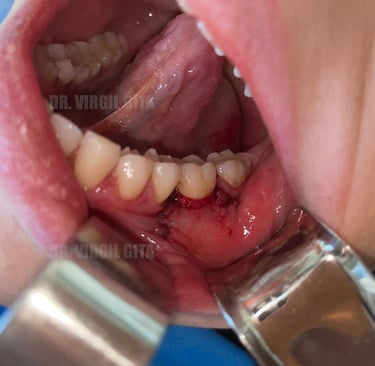

Tratament retractie gingivala post tratament ortodontic cu lambou tractionat coronar si grefa de tesut conjunctiv prelevata de la nivelul palatului + membrana PRF